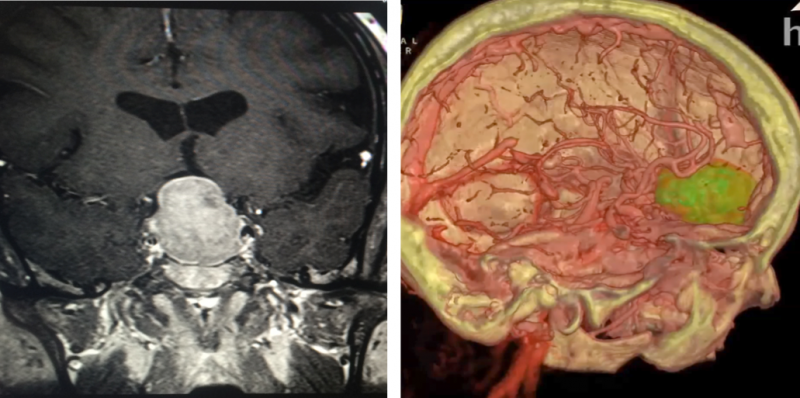

The same virtual reality (VR) reconstructions that surgeons use to plan and rehearse brain surgeries at Hoag Memorial ...